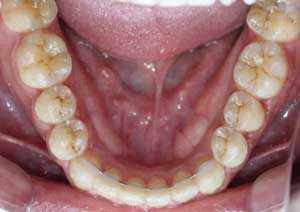

Traitement : Dans ce cas, nous avons eu recours à la mise en place de cales postérieures en résine bleue au niveau des premières molaires maxillaires, Elles ont permis de séparer temporairement les mâchoires afin de laisser les dents du haut se replacer correctement devant celles du bas, corrigeant ainsi le cross-bite antérieur.

Par la suite, ces cales ont été déplacées sur les faces palatines des incisives maxillaires dans le but d’optimiser l’articulé postérieur, notamment au niveau des molaires droites, qui présentaient également un articulé inversé.

Avant

Après